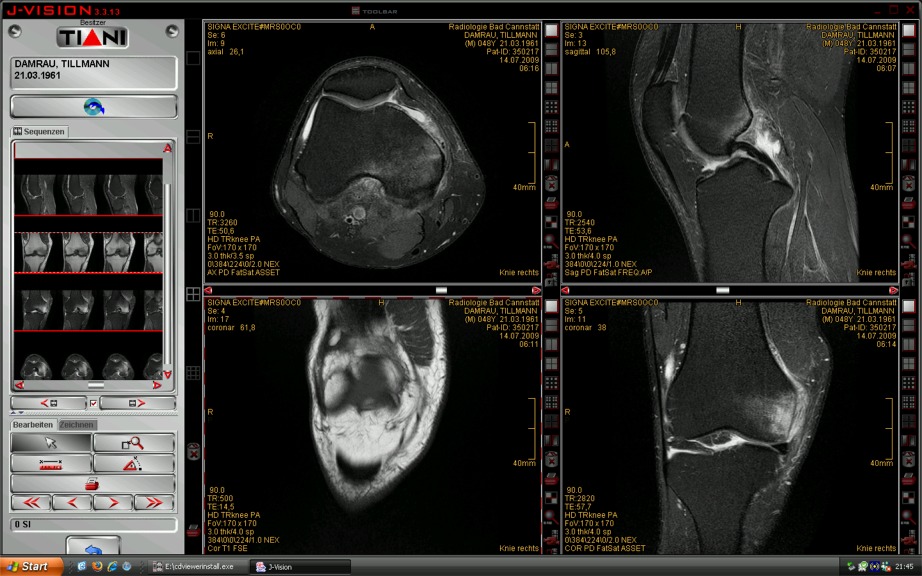

Schwarzweiße Bilder zur Lage – nicht, wie ich dachte, bunte – fand ich auch auf der CD mit den Aufnahmen von meinem Knie. Neugierig hatte ich die CD zu Hause am PC gleich eingelegt um die Aufnahmen am Bildschirm anzuschauen. Ein wenig gestaunt habe ich, dass auf der CD nicht nur eine puristische Sammlung von Ordnern mit rätselhaften Bildern zu finden war. Im Gegenteil, ein Programm öffnete eine Benutzeroberfläche mit vielen interaktiven Funktionen.

Was ich am Bildschirm vor mir sah, war ein weiteres Beispiel für die eminente Wichtigkeit der Multifunktionalität von Bildern gerade im Cyberspace. Diese Multifunktionalität reicht von einfachen navigatorischen Funktionen bis hin zum „Naturalismus“ der Aufnahmen des Knies, die der diagnostisch geschulte Arzt aber wiederum ganz anders wahrnimmt als ein Laie.

Ein Laie, mag sein, ist viel empfänglicher für das gespenstisch Seltsame der Bildsequenzen, vor allem, wenn er – ohne dass ihm die Bilder in einem spontanen, intuitiven Sinn „ähnlich“ wären – diese dazuhin noch mit dem eigenen Körper und Befinden zu korrelieren hat.

Bemerkenswert finde ich, dass man sich nicht mit einer einfachen grafischen Benutzeroberfläche zufrieden gegeben hat. Auch in der Medizin scheint Gestaltung bei der digitalen Visualisierung über das rein Organisatorische hinaus wichtig geworden zu sein.

In diesem Fall bemühte man um ein Design mit der Anmutung kühler Professionalität, dazu passend wurde das interaktive Bild eines metallenen Bedienungspaneels programmiert, bei dem auch Nieten in der Abdeckung oben und unten nicht vergessen wurden. In der Grundeinstellung ist es links von den Feldern des Splitscreens mit den Aufnahmen platziert.

Offensichtlich ging es nicht nur darum, die Resultate eines bildgebenden Verfahrens medizinischer Diagnostik zugänglich zu machen, sondern der Rezeption mittels der Bildschirmdarstellung auch einen ästhetischen Kontext zur Verfügung zu stellen, der bloß praktische Erwägungen sichtlich übersteigt.